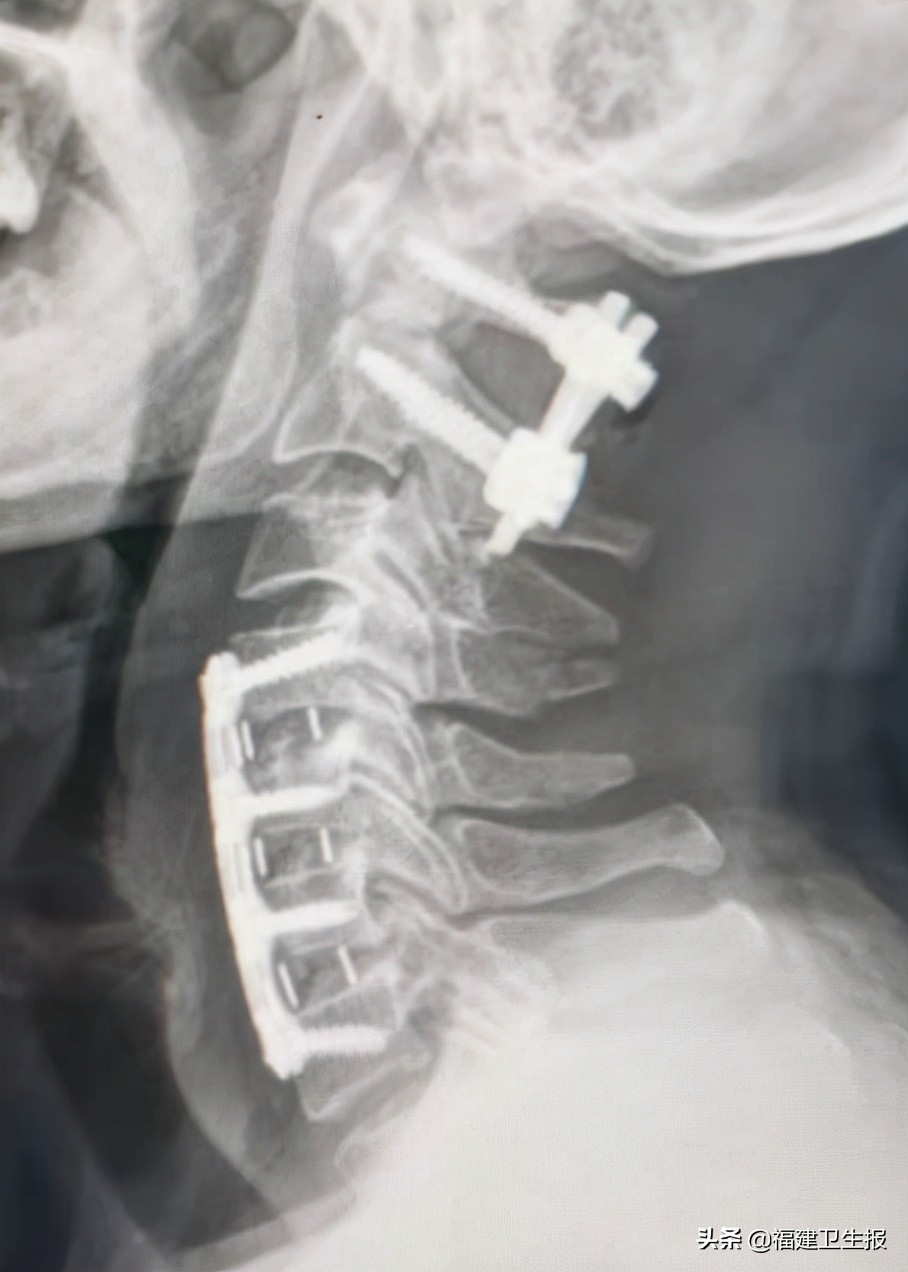

术后患者很快恢复清醒,四肢开始活动。术后第一天患者双上肢可自行举起,双手握力开始恢复。术后第5天患者各引流管均拔除,佩戴颈托自行下地步行良好,双上肢肌力恢复正常,下肢肌力正常,各项生活可自理,复查颈椎X线片及颈椎CT见枢椎齿状突骨折及寰椎复位良好,内固定精准在位。

▲术后复查颈椎X光